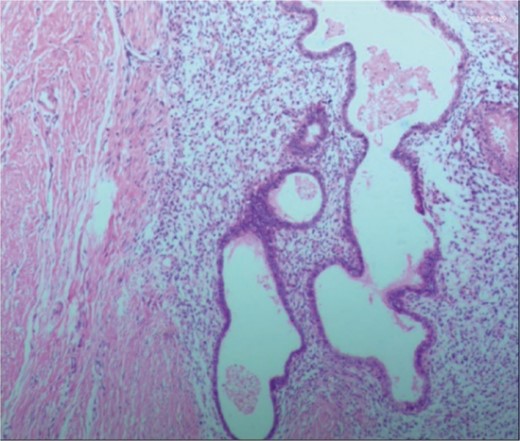

A 38-year-old married female patient presented with a lump near her anus 10 years ago, without apparent cause or symptoms such as redness, swelling, heat, or pain, nor cough, abdominal pain, or diarrhea. No specific treatment was administered. The patient now reports that the lump has grown larger and is accompanied by increasing swelling and discomfort. Seeking further diagnosis and treatment, she visited our outpatient department, where she was admitted with the condition “perianal lump.” Physical examination revealed a body temperature of 36.5°C, pulse rate of 86 beats/min, respiratory rate of 19 beats/min, and a blood pressure of 134/85 mmHg. Admission symptoms include perianal swelling and pain, with itching; no signs of fever, chills, rupture, or pus discharge; bowel movements once or twice daily, and normal urination. The patient has one child and underwent a lateral epidural resection 12 years ago due to natural childbirth. Specialist examination revealed a 4-cm lump with a hard texture at 7–11 o’clock next to the anus, and a radial surgical incision at the 7 o’clock anal margin. Digital rectal examination found no lump, depression, or induration in the anus, and no blood on fingertips. The initial diagnosis was a perianal lump. Auxiliary examinations included ultrasound, which revealed a 4-cm lump in the subcutaneous soft tissue near the anus with minor blood flow signals within and around it, suggestive of an inflammatory lesion (Fig. 1A and B); and pelvic MRI, which suggested a left perianal lump consistent with a perianal abscess (Fig. 2A and B). Under spinal anesthesia, the perianal lump was removed, and postoperative pathology confirmed the presence of endometriosis (Fig. 3).

Ultrasound: (A) 2D ultrasound shows a mixed echo with a range of about 4 cm in the subcutaneous soft tissue around the left side of the anus, presenting as cystic-solid; (B) color doppler shows a small amount of punctate blood flow signal inside and around the mixed echo.

Postoperative pathology: the endometrial glands have typical stroma, blood, and macrophages containing hemosiderin.